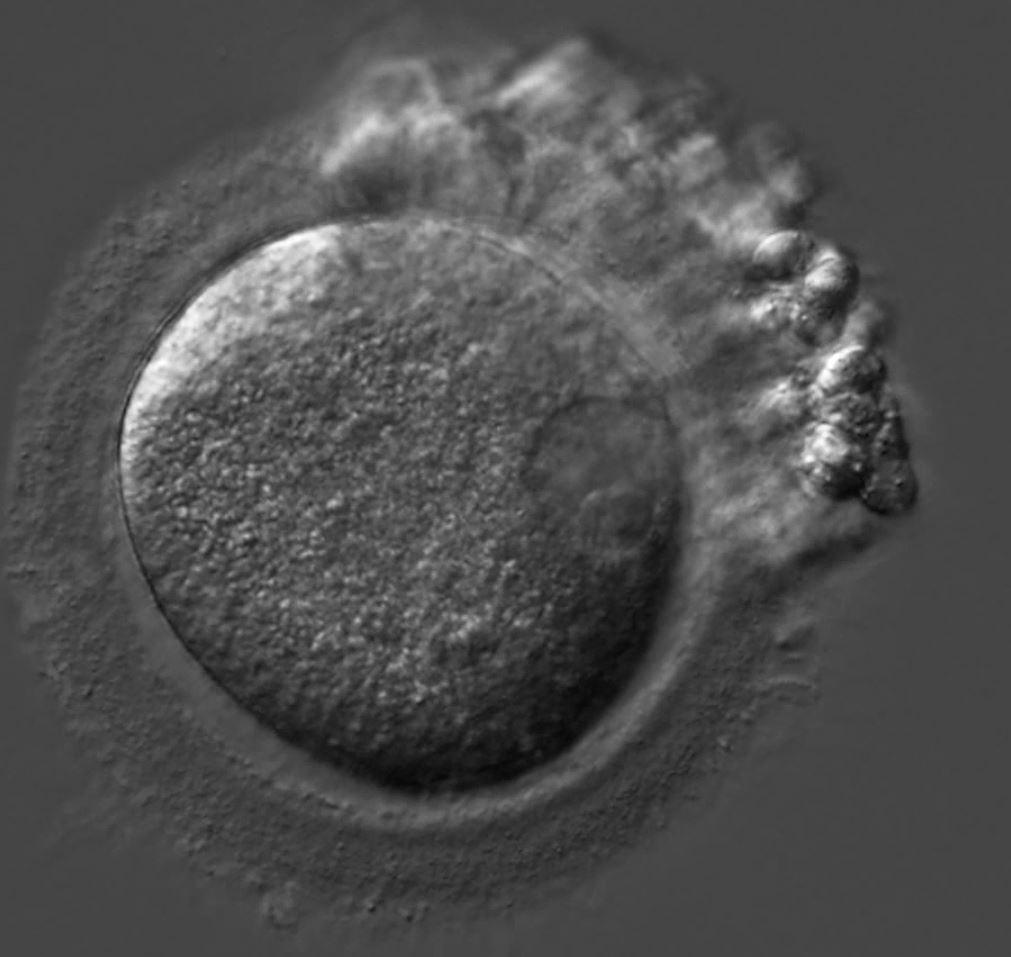

Patients arrive for egg retrieval at the CHR hoping that the physicians and embryologists will bring good news to them soon. This image, taken at the CHR, illustrates the first signs that good news is on the horizon. It depicts a freshly retrieved cumulus-oocyte complex with the oocyte seen as a large central sphere partially obscured by the thousands of cumulus cells radiating outwards. As noted before in The Voice, the next step is for the embryologist to remove these cells so they can further evaluate the health and maturity status of oocytes, which if mature, will then undergo ICSI to launch embryonic development.

What happens when the cumulus cells are removed? This image shows that sometimes it is difficult to remove all of the cumulus cells as seen at 12-3 o’clock. Note that at 3 o’clock a single round nucleus is evident which tells us that this oocyte has not yet completed the maturation process that should have been triggered by the last injections. In fact, this is what we call an immature GV (germinal vesicle) stage oocyte that would have undergone overnight rescue maturation before attempting ICSI the following day.